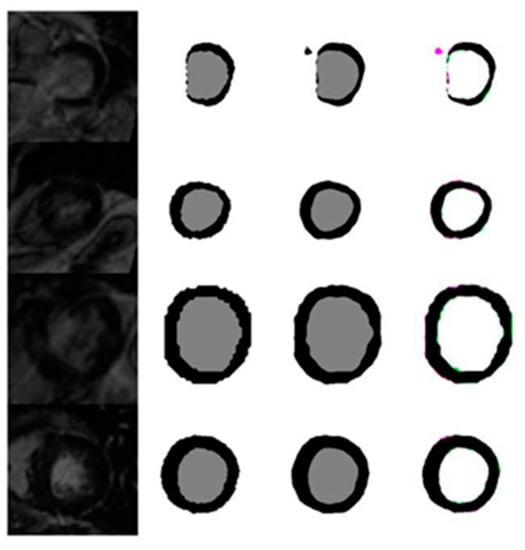

4.1. Evaluation of the Effects of Image Size on the Quality of Automatic Segmentation with U-Net against the GT Segmentation

4.1.6. Evaluation of Automated Segmentation with U-Net and GT Segmentation Using LGE MRI Test Images